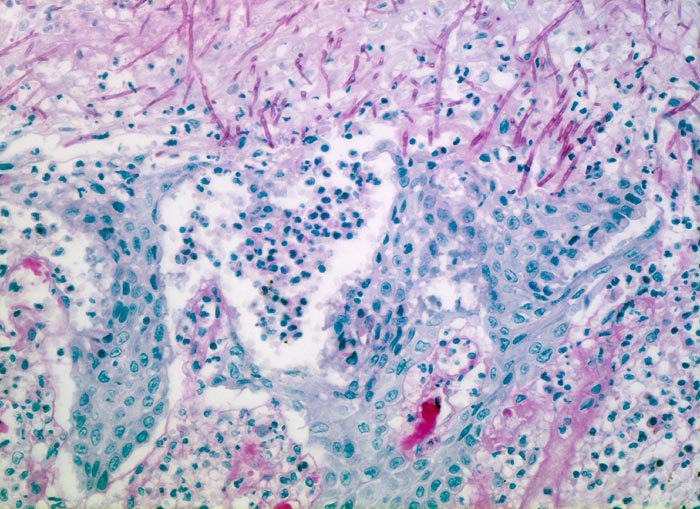

• Die Pseudomembran über der ulzerierten Schleimhaut setzt sich zusammen aus einem dichten Netzwerk PAS positiver Soorpseudohyphen und ovale aussprossende Sporen, nekrotischem Plattenepithel, Fibrin und neutrophilen Granulozyten.

• Die Pseudohyphen infiltrieren das Plattenepithel.

• Im Unterschied zur Aspergillose dünnere Pseudohyphen ohne echte Verzweigungen und zahlreiche Sporen.

• Verdacht auf Soorinfektion (Pilze besser nachweisbar in der PAS oder Grocottfärbung als in der routinemässig angefertigten HE Färbung).